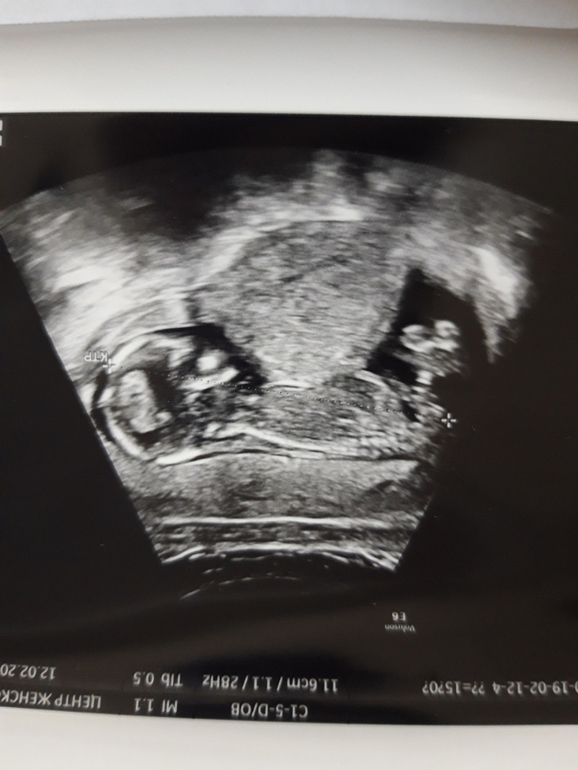

На девочку похоже, у вас двурогая матка? По сниму над животом ребенка не могу понять что)

А там, где хозяйство должно быть, там и половой бугорок). По вашему фото похоже на девочку.